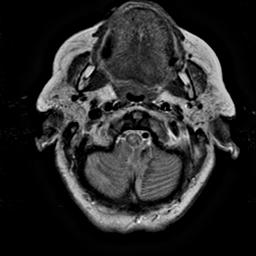

To demonstrate the effectiveness and efficiency of the proposed image fusion method , we conduct a set of comparative experiments on three image datasets. The first is composed by 8 pairs of multi-modal medical images and the second one contains 15 pairs of multi-focus gray or color natural images. These two datasets are often used in many related papers and some examples are shown in Figure 3(a) and Figure 3(b). The third one is a new multi-focus cervical cell image dataset collected by ourselves, which consists of 15 groups of color images and each group contains a series of multi-focus cervix cell images with size of or , etc. Some source examples are shown in Figure 3(c). Our source code implemented in C++ along with the new multi-focus cervical cell image dataset is available online.

We first evaluate the performance of the proposed method under varying total number of octaves and number of layers sampled per octave. The fused images of a pair of multi-modal medical images with different and are shown in Figure 4. In this example, on the one hand, when only 1 or 2 octaves are involved in constructing the DoG pyramid, the fused images fail to keep the integrity information of large size objects (e.g. eyeballs), while by increasing the value of , the integrity information of eyeballs is preserved. On the other hand, although not as significant as the increase of octave numbers , the fused image can contain more details by the increase of layer numbers . The corresponding objective quality metrics are shown in Figure 5. As shown in Figure 5(a), most of the metric values are improved as the number of octaves increases with the fixed layer numbers 3 in the global tendency and each of them tends to be stable when the number of octaves is 5. To get a relatively good quality from Figure 5(b), we can notice that some of the metric values can get a good performance when the number of layers is 3, such as the MI, SSIM, QI and VIF, though there are only a little change of all the metric values by increasing the number of layers with the fixed octave numbers 5. Because it will result in more computation burden with the increase of the value and , and for different kinds of source images, there are different performance with the diverse parameter settings. To get a trade-off between them in our experiments, we set for the multi-modal dataset, for the natural datasets and for the multi-focus cell dataset, respectively.

Figure 6 shows the fused images obtained by different methods with the multi-modal source images shown in Figure 3(a). As shown in these figures, the proposed method can produce images which preserve the complementary information of different source images well. Moreover, due to the scale-invariant structure saliency selection, our method can keep the integrity information of large size objects and the visual details simultaneously. Although the fused image generated by other methods can also capture the details to some extent, all of them fail to keep the integrity information of large size objects such as the eyeballs. Furthermore, from Figure 6(k)-6(t), the DTCWT, GFF, IM and NSCT methods may decrease the brightness and contrast while the proposed method can preserve these features and details without producing visible artifacts and brightness distortions.